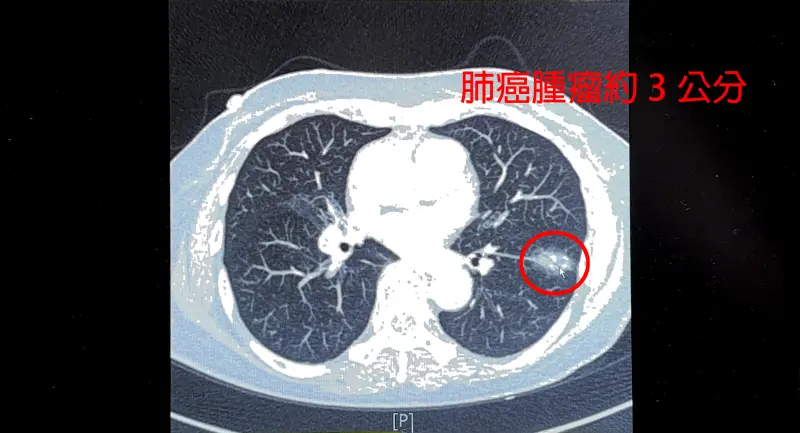

一名75歲女性從不抽菸、喝酒,日前健檢接受低劑量電腦斷層(LDCT)檢查,意外發現左下肺葉有接近3公分的惡性腫瘤,而因10多年前曾罹患肺結核,導致肺部留下堅硬病灶,在這種狀況下手術風險極高,所幸在達文西機器手臂輔助下順利完成切除,術後恢復良好,3日後便順利出院。

中國醫藥大學新竹附設醫院胸腔外科主治醫師謝義山說,患者曾有肺結核,導致縱膈淋巴結非常堅硬,且與血管嚴重沾黏,若進行手術,稍有不慎便可能造成大量出血,故這次透過機器手臂進行血管分離與結紮,即使過程中有2條分支破裂,仍成功止血,總出血量僅200cc。